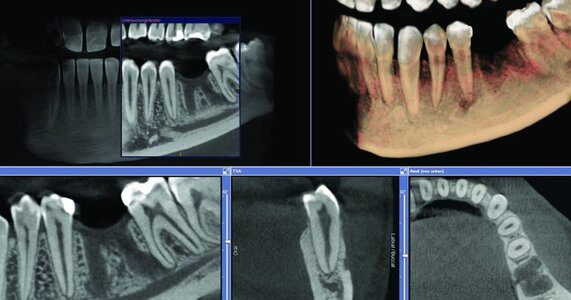

Traditional dental X-rays provide a two-dimensional view of the teeth and jaw, which often limits the dentist’s ability to assess critical details. In contrast, CBCT captures detailed 3D images of the entire oral cavity, including teeth, bone, nerves, and sinus cavities. This advanced imaging produces a comprehensive map, enabling dentists to plan implants with exceptional precision.

CBCT scanners rotate around the patient’s head, capturing hundreds of images in a single scan. These images combine to create a three-dimensional digital model. Unlike conventional CT scans, CBCT uses a lower radiation dose, making it safer for dental applications while still providing high-resolution images crucial for implant planning.

While traditional X-rays still have a role in dental care, CBCT surpasses them in implant planning. Two-dimensional images cannot capture depth or detect overlapping structures. CBCT eliminates guesswork by providing an accurate 3D map of the patient’s oral anatomy.